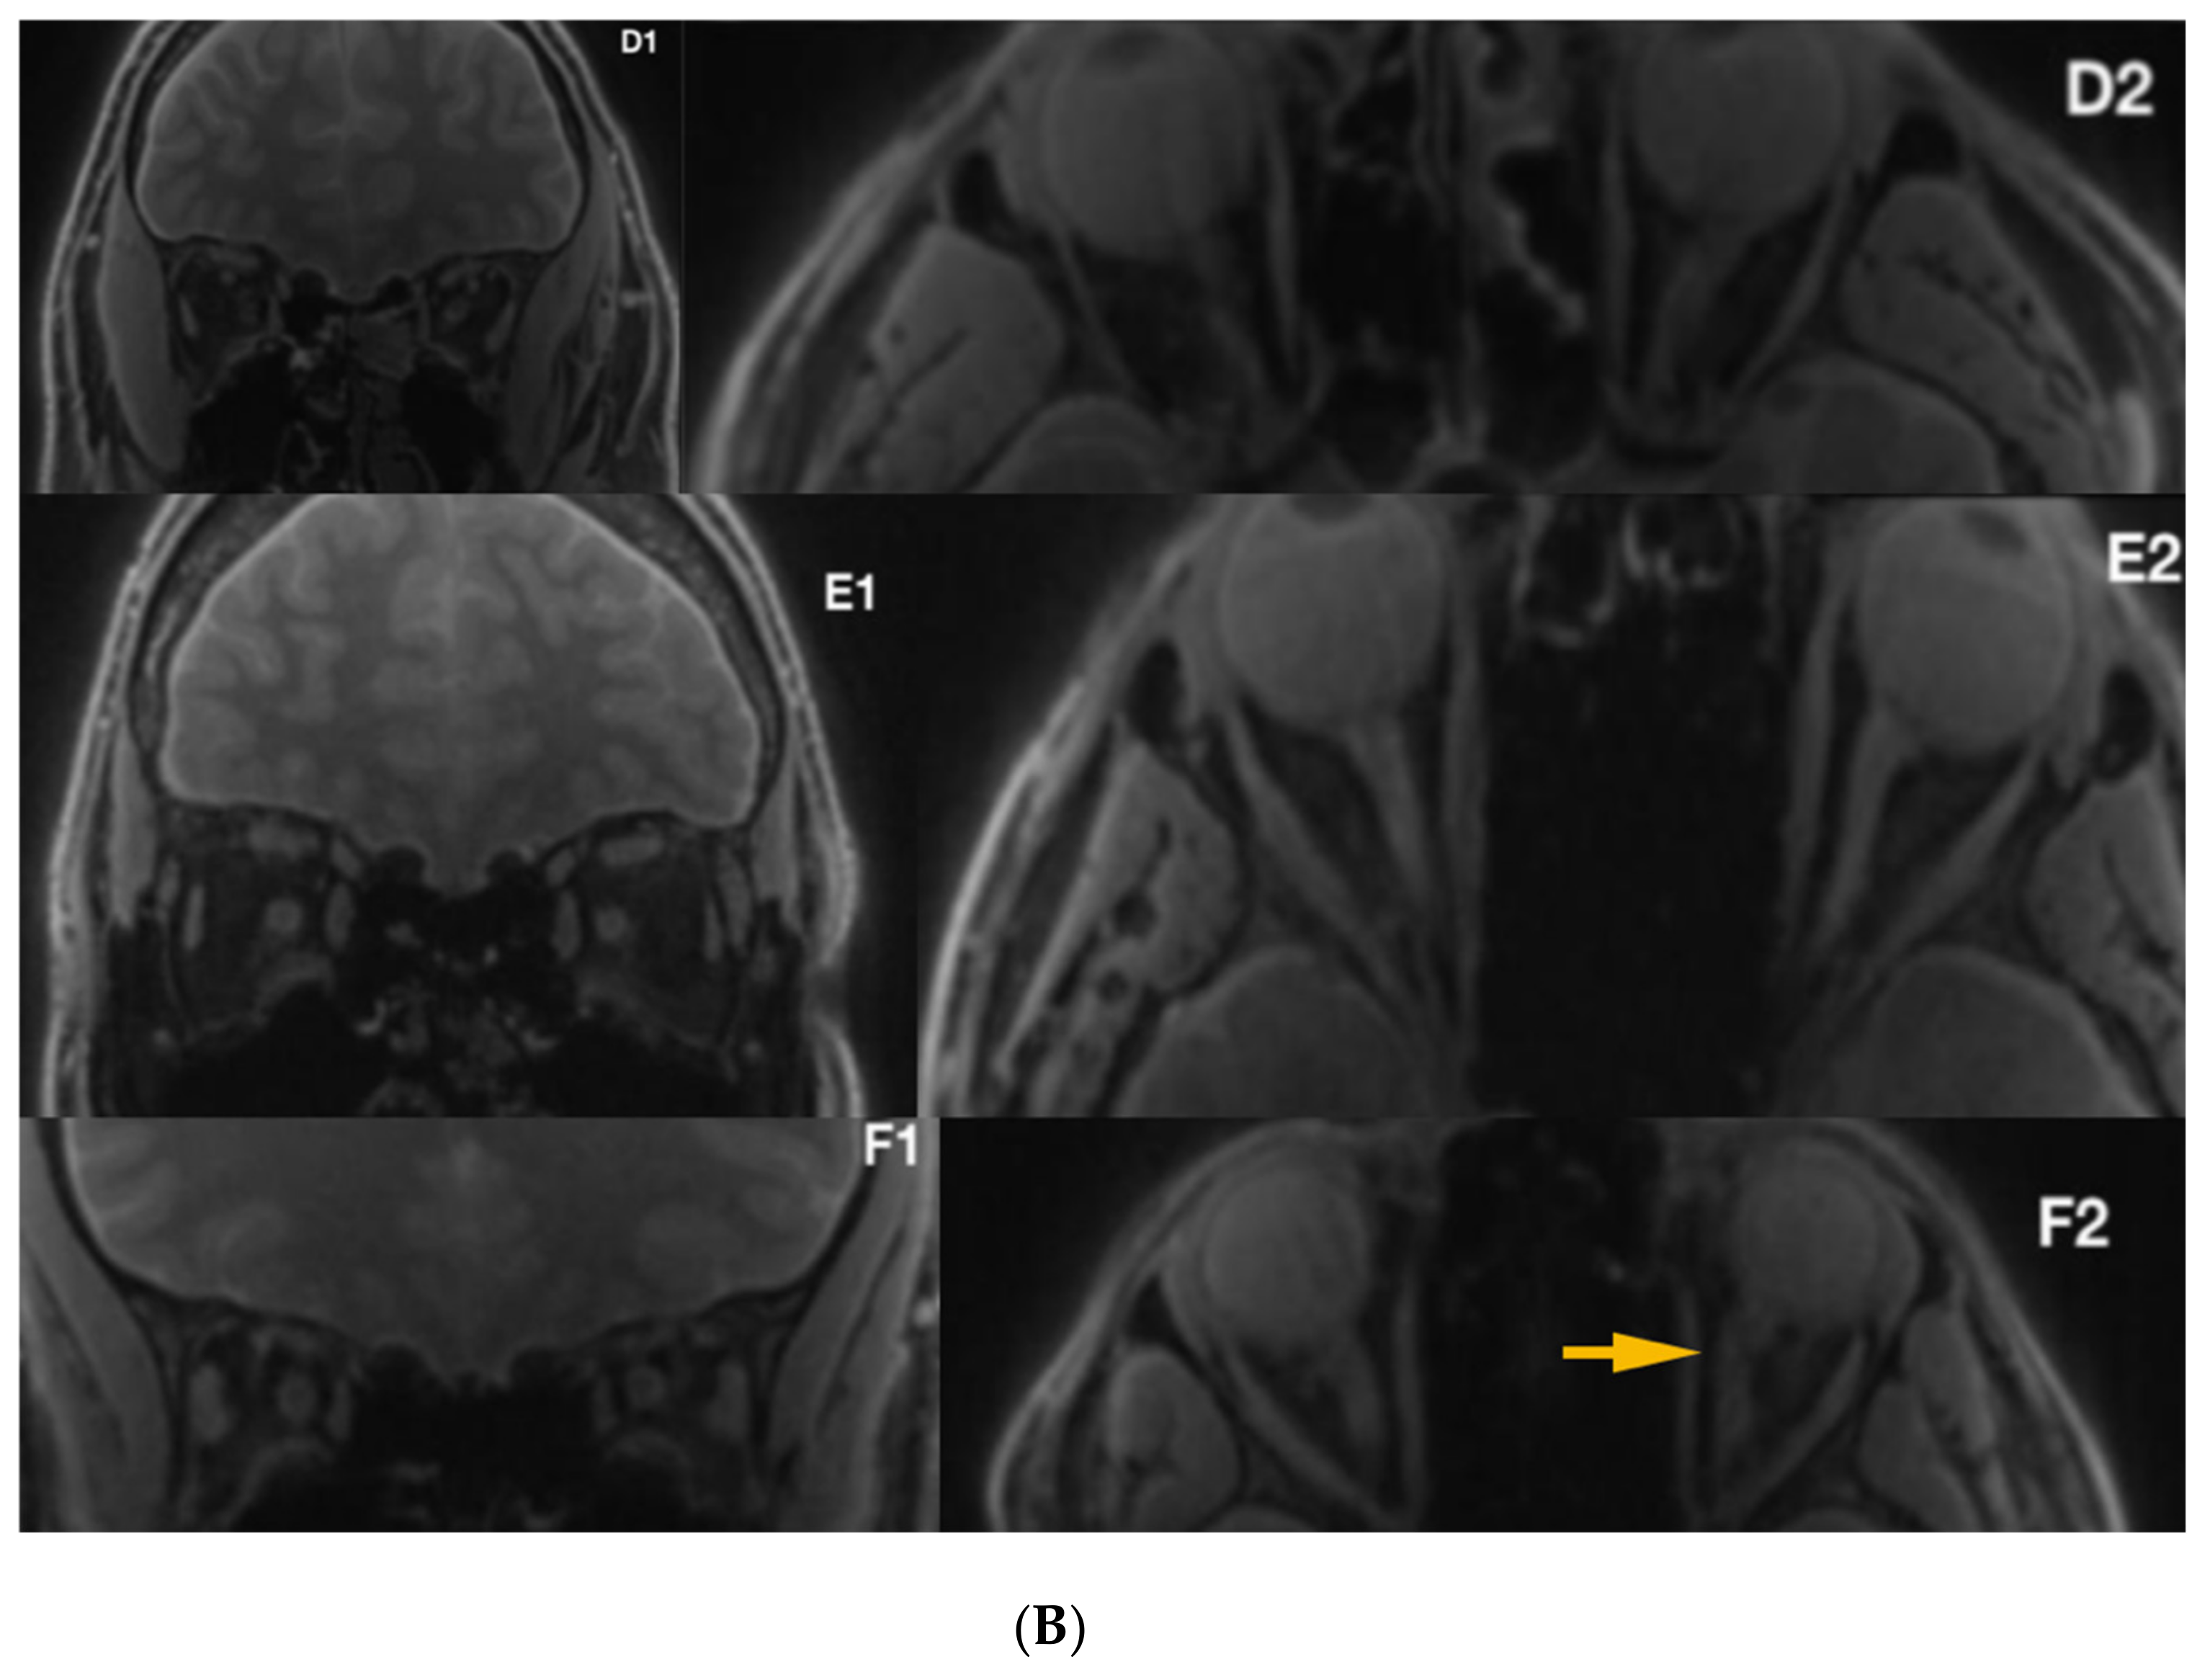

3.1. Radiological Inspection